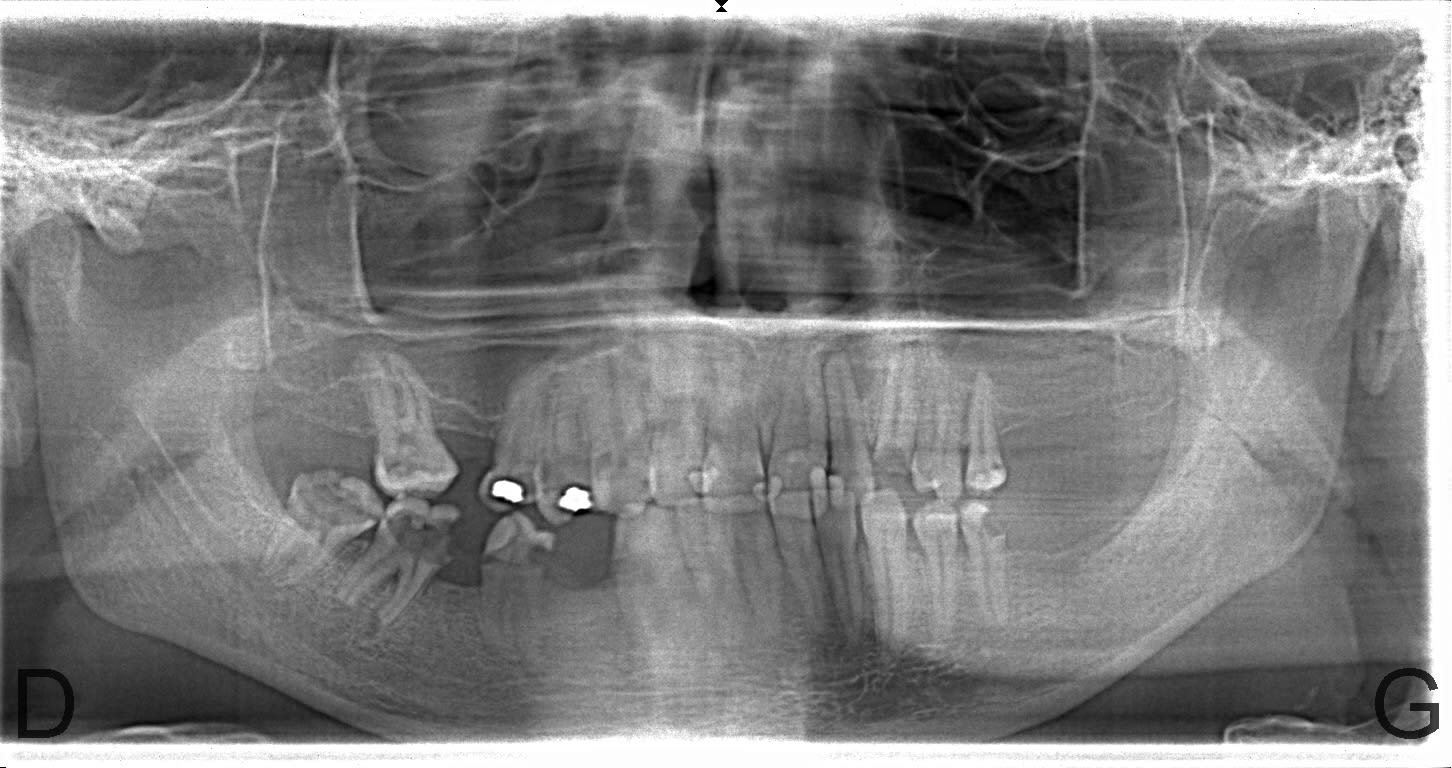

Des comme ça j'en 2 ou 3 par semaine (vu à l'instant ) ... Petite question : quel âge à ce patient ? Deuxième question à Carident et à quelques autres, quel est le montant de votre plan de traitement ? ( je ne demande pas le détail )(@ lardon , la 15 en métal , marqueur social ? ) .. troisième question : pensez vous que ce patient a la mutuelle adéquate à son état dentaire et enfin : pensez-vous que ce patient serait mieux pris en charge grâce au RAC 0 ? On va faire dans le concret de pas mal de cabinet dentaire ....

Pour l'age, c'est pas pour l'expulser, mais c'est impossible à dire par rapport à la radio. Au delà de 18 ans, c'est certain, tu ne sera pas arrêté pour détournement de mineur.

Puisque tu en parles, ca doit être la trentaine. Il a eut différentes extractions réalisées au cour du temps et à abandonné déjà les soins en cours de route.

C'est bien pour cela que c'est impossible de parler de devis et de tarifs, puisque quelque soit le devis, les probabilités d'arriver au bout du plan de traitement sont faible et il abandonnera bien avant les prothèses sur des soins opposables ce qui montre que le tarif et les remboursements ne sont pas en cause.

26/02/2018 à 12h12

Age 19 Ans ! , et bien sûr qu'il ira au bout du traitement s' il peut financièrement ! Il est motivé , c'est un jeune homme "bien" . sérieux , il est à l'heure , n'est pas peureux .. bref , ce genre de patient où tu sais pertinemment que ce qui va coincer c'est l'argent . Barba , il existe des patients non serieux à tous les niveaux de la société et quand c'est un cadre , là , on pense qu'il n'a pas le temps . Alors , on fait quoi pour ce jeune , on le prend en charge ( nous la société ...) ? on lui dit que c'est trop tard ? t'avais qu'à te brosser les dents ? ( vous avez remarqué qu'il a eu déjà de nombreux soins ) . Et, s'il vous plait, gardez pour vous vos généralisations à 2 balles ! ( barba , tu me suis ? ) . Ah ouais aussi , je ne lui ai pas mis un devis sous le nez avant de commencer à le soigner .. évidemment !

Je précise aussi , ce patient n'est pas venu parce qu'il avait mal .... étrange , non ?